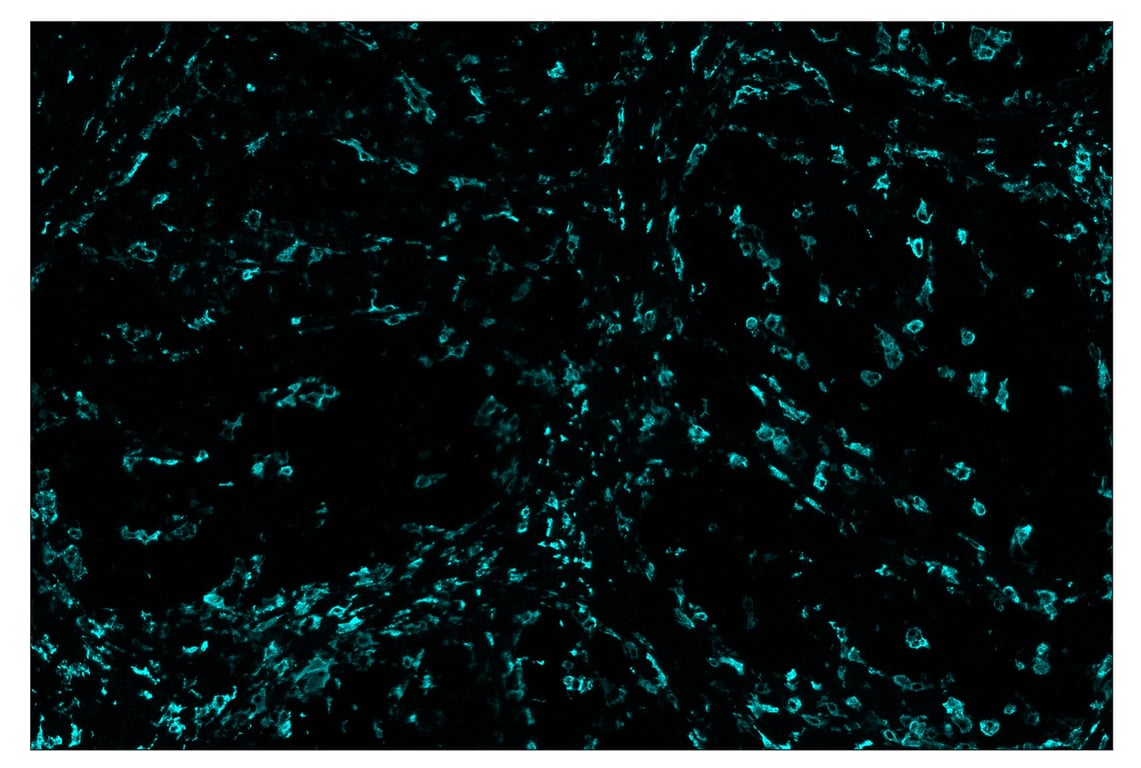

SignalStar™ immunohistochemical analysis of paraffin-embedded human gastric adenocarcinoma using CD163 (D6U1J) & CO-0022-750 SignalStar™ Oligo-Antibody Pair #71043 (cyan). All fluorophores have been assigned a pseudocolor, as indicated. Staining was performed on the BOND RX by Leica Biosystems.

Immunohistochemistry Image 5: CD163 (D6U1J) & CO-0022-594 SignalStar<sup>™</sup> Oligo-Antibody Pair